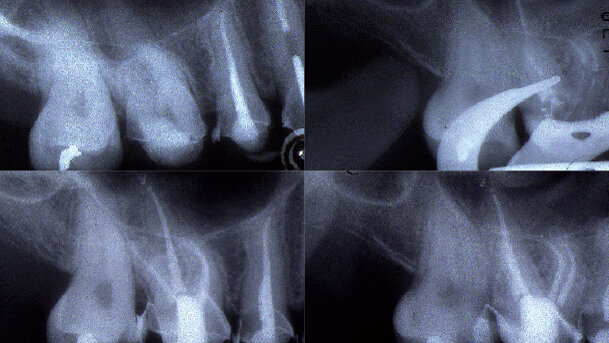

Obr. 7: Postranní řezák 17letého pacienta, poškozeného před několika lety úrazem a bez vitální pulpy, s chronickou progresivní zánětlivou lézí endodontického původu.

Obr. 8: Zavedení nástroje AS 30 bez tlaku, apikální průměr přesahující ISO 25 vyžaduje preparovat AS 40 na PD.

Obr. 9: Zavedení hlavního čepu (6 %, Nr. 40)

Obr. 10 Rentgenový snímek bezprostředně po výkonu (laterální apikální kondenzace a termoplastická technika plnění ve střední a koronální třetině kanálku).

Obr. 11: Kontrolní rtg snímek po třech měsících: je patrné počínající hojení periapikální krajiny